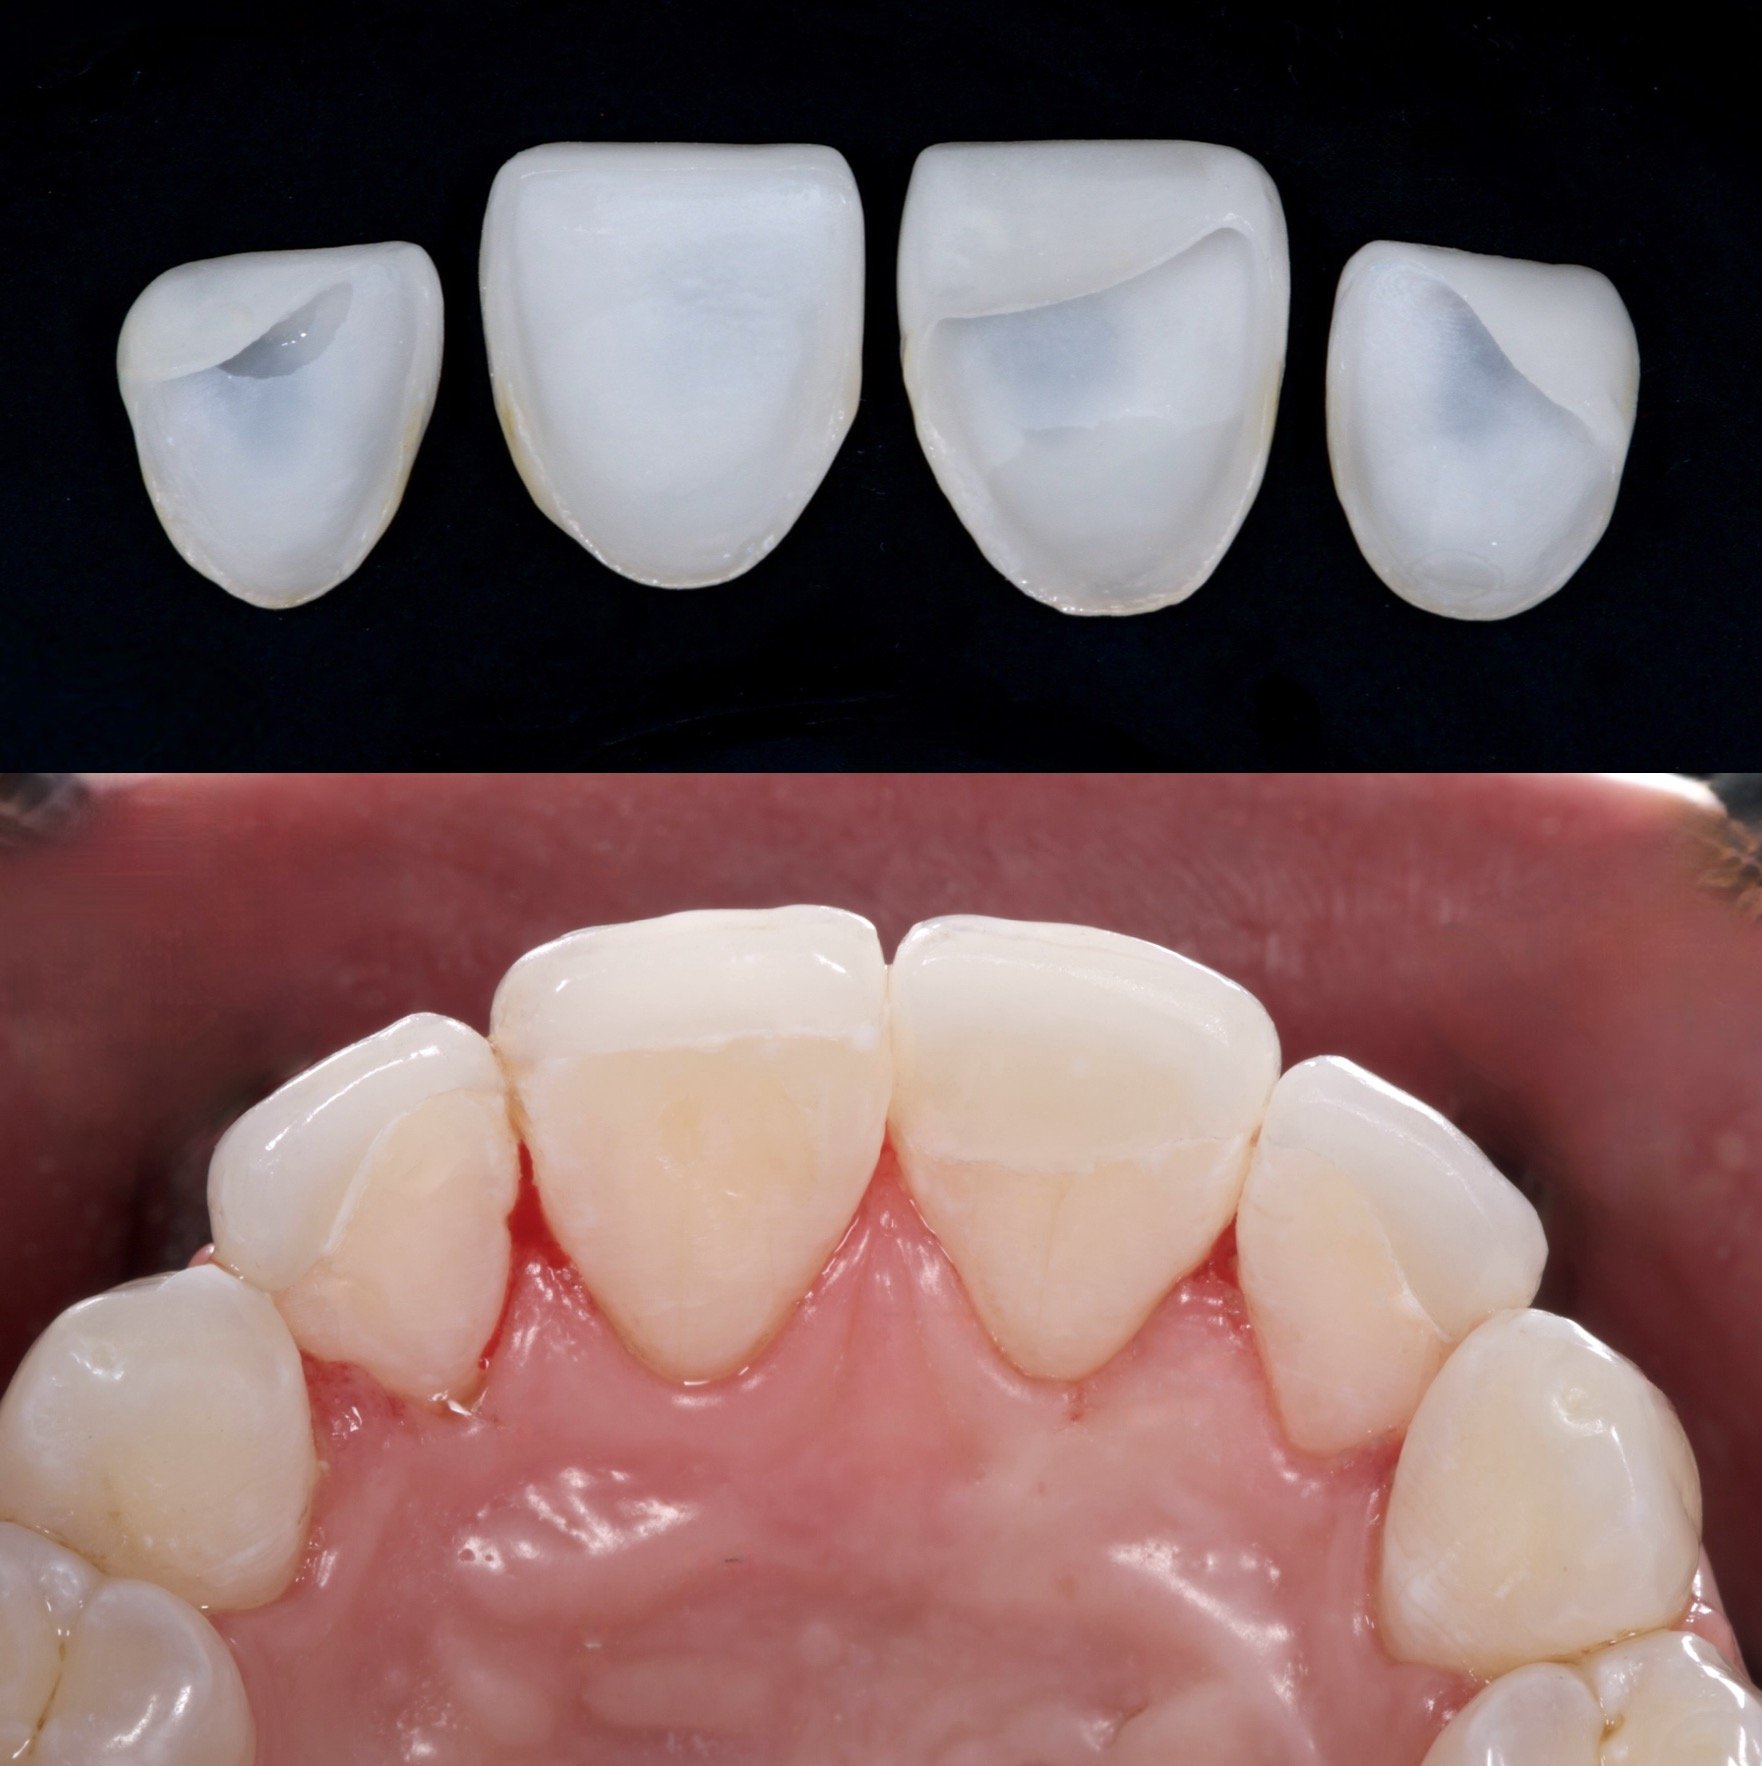

4 Minimal Prep Veneers in Shade 0.5M1

Dr. Heldt, 2025. Newport Beach, California.

Because the patient is not interested in orthodontics, we were able to have the teeth appear straightened with 4 veneers. This is not the doctor’s recommendation by the way. 4 Layered eMax Veneers (#7-10) in Shade 0.5M1. Diagnostic waxup with patient-approved temporaries for shape and shade. Low translucency. No staining.